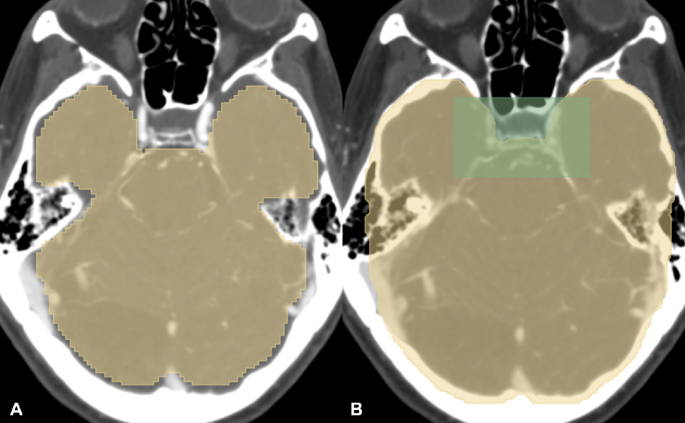

Brain mask

To suppress detections outside the intracranial region, we incorporated patient-specific brain masks into the heuristic post-processing module. These masks were used to remove bounding boxes located outside the brain. Each brain mask was generated from the inference (test) CTA using the TotalSegmentator library (Fig. 3A)14. This mask was dilated 3.6 mm (9 pixels) in 3 dimensions to ensure inclusion of all intracranial structures and then combined with the CVS region bounding box to ensure inclusion of appropriate skull base structures (Fig. 3B).

Brain segmentation mask using TotalSegmentator (A), dilated 3.6 mm in each direction (yellow in B). The cavernous venous sinus (CVS) region bounding box from Fig. 2B (green) was added to the brain mask to ensure inclusion of the appropriate skull base structures (B).